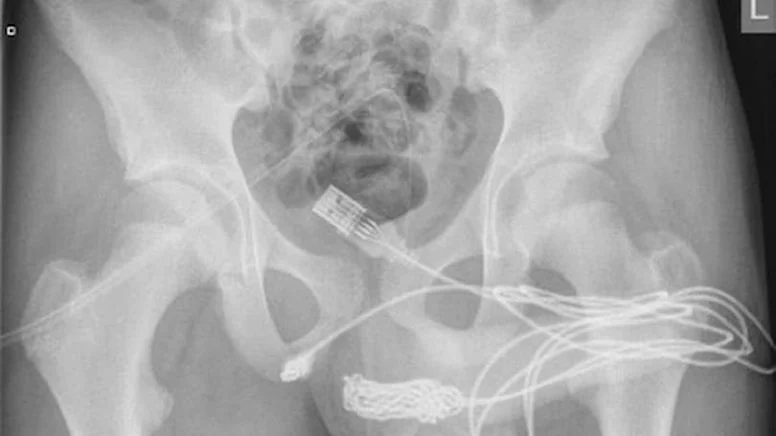

Yaşadığı olayı kaldırıldığı hastanede doktorlara anlatan gencin röntgen sonucunu inceleyen bilim insanları ise şaşkına döndü. “Cinsel deney” uğruna sağlığını riske atan gencin penisinden USB kablo zorlukla çıkarıldı.

Ameliyatı gerçekleştiren doktorlar durumu kamuoyuna hazırladıkları bir rapor ile duyururken, USB kablolarının vücut içinde düğüm olduğunu ve bu sebeple ameliyatın büyük bir zorluk içerisinde gerçekleştiğini açıkladı.

Science Direct isimli medya platformunun Urology isimli bilimsel dergiden hazırladığı haberde yer alan bilimsel araştırmada olayın 2021’de meydana geldiği belirtildi. Doktorların kaleme aldığı bilimsel araştırmada, “Vücuda yerleştirilen cisim derin doku üzerinden çıkarıldı. Kablolar penis ucundan çıkarıldı” denilirken ismi açıklanmayan gencin cinsel deney için bunu yaptığı ve herhangi bir zihinsel rahatsızlığı olmadığı da duyuruldu